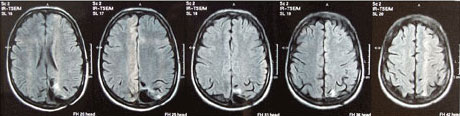

Die routinemäßige Kontrolluntersuchnug mittels Computertomographie, 3 Tage postoperativ, zeigte ideale Verhältnisse (ca. 45mm großer Operationsdefekt links occipital mit einzelnen Lufteinschüssen);

MRT-Bilder postoperativ (nach der Operation)